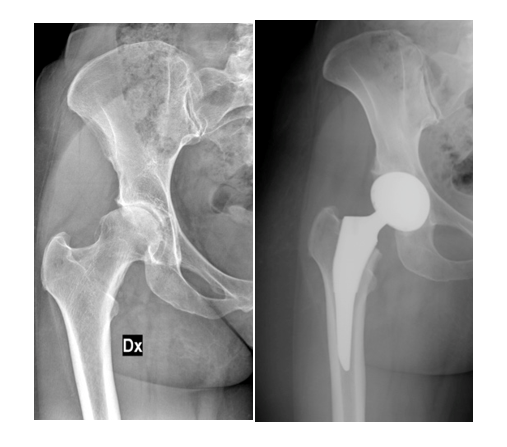

L’anca è una delle articolazioni più importanti del nostro corpo: sostiene il peso e consente ogni movimento. L’artrosi dell’anca consiste nella progressiva usura della cartilagine che riveste l’articolazione tra il femore e l’acetabolo del bacino.

Quando il dolore diventa persistente e limita la vita quotidiana, la protesi d’anca rappresenta l’unica soluzione efficace per eliminare il dolore e recuperare la mobilità.

Protesi d’anca non cementata

La protesi viene fissata con tecnica press-fit, permettendo all’osso di integrarsi naturalmente con l’impianto, garantendo stabilità e durata nel tempo.

Il successo clinico e la durata dell’impianto dipendono in modo determinante da una rigorosa pianificazione pre-operatoria. Attraverso lo studio analitico dell’anatomia del paziente, l’ortopedico è in grado di definire una strategia chirurgica personalizzata, garantendo i massimi standard di precisione. Scopri di più QUI.

L’evoluzione classica di un’artrosi dell’anca (coxartrosi) è la scomparsa progressiva della cartilagine fra l’osso della coscia (femore) e quello del bacino. Clicca QUI per saperne di più